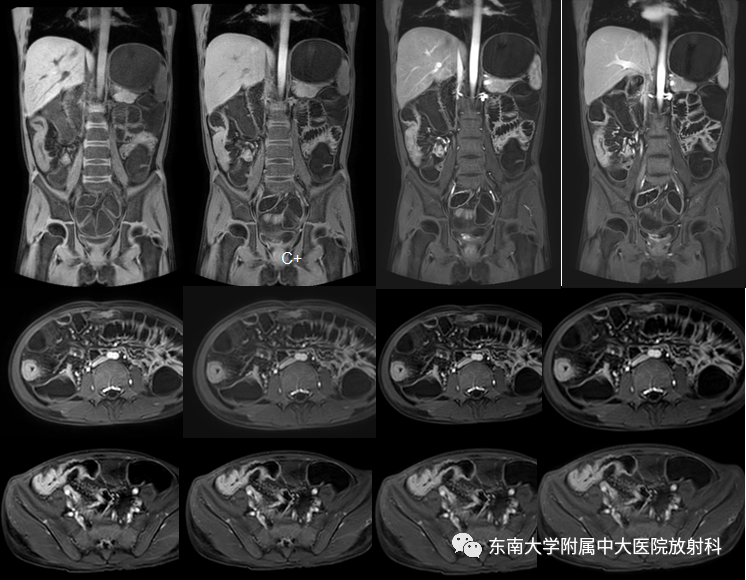

克罗恩病

病例

•男,14岁

•主诉:因“间断腹痛1年,加重伴大便次数增多1月”入院

•患者1年前无明显诱因下出现腹痛,主要位于脐周,呈阵发性发作,未予重视。1年来症状时有发作,约1-2次/周,未正规就诊治疗。1月前患者自觉腹痛加重,伴有大便次数增多,约3次/日,稀糊状。外院胸腹部CT:1、胸部平扫未见异常;2、升结肠及部分横结肠管壁增厚,考虑克罗恩病可能,建议肠镜检查。彩超:肝胆胰脾未见异常。予以“甲泼尼龙、奥硝唑、头孢”等治疗5天,后腹痛症状有所缓解